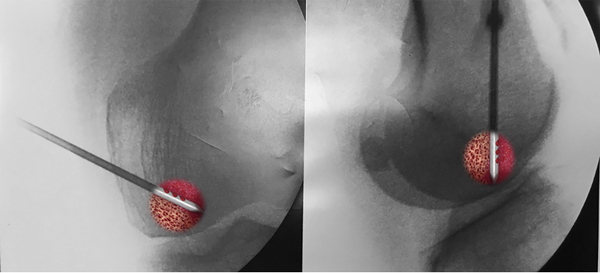

Bajo anestesia regional o espinal, el paciente es colocado en posición supina como para la artroscopía estándar de rodilla. Antes de la inyección de BMA, se debe tratar cualquier anomalía concomitante, como lesiones condrales, desgarros meniscales y lesiones de ligamentos. La alineación de las extremidades juega un papel crucial en el tratamiento de la lesión del cartílago, por lo tanto, cualquier deseje debe ser tratado también. Se utiliza un artroscopio de 4 mm y 30° (Smith & Nephew, EE. UU.) para realizar un examen artroscópico completo de la rodilla. Las imágenes fluoroscópicas anteroposteriores (AP) y laterales con referencia cruzada con el estudio de resonancia magnética se utilizan para colocar el pasador guía con precisión en la LMO. Luego se coloca una cánula sobre el pasador guía, que posteriormente se retira. Se deja durante unos minutos en el hueso para realizar la descompresión del núcleo.

A continuación, se insertan las clavijas óseas en la cánula y se empujan a través de la lesión subcondral con un trocar romo. Luego, el BMA se inyecta a través de la cánula en el área tratada (fig. 6). Se realiza una mirada artroscópica final para confirmar la usencia de fuga intraarticular.

Figura 6: Imagen coronal (A) y sagital (B) de rodilla por fluoroscopia que muestra la infiltración intraósea de médula ósea aspirada o concentrada (BMA/C) en un cóndilo femoral.